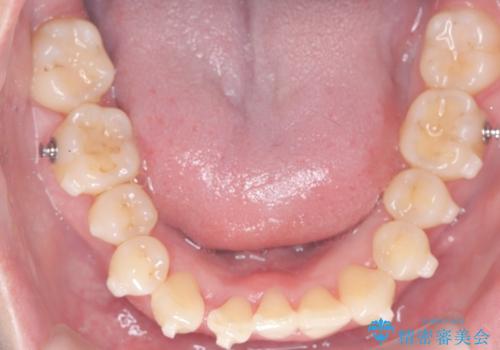

- 患者様は、下顎前歯のガタつきを改善したいとのことで来院されました。診察の結果、スペース不足により前歯が重なっている状態でした。抜歯をせずに並べると前歯が前方に突出してしまうため、下顎の前歯を1本抜歯し、インビザラインで矯正する治療計画を立てました。できる限り追加のアライナーを使用せずに治療を完了できるよう、初回の治療計画を慎重に設計しました。

下顎前歯を1本抜歯し、歯列のスペースを確保。その後、インビザラインを用いて計画通りに歯を移動させ、噛み合わせも整えました。患者様の協力もあり、ゴムかけなどを適切に行い、予定通り1年で治療を完了。追加アライナーを使用することなく、計画通りに治療を終えることができました。患者様からは「思ったより早く終わり、仕上がりにも満足している」と喜びの声をいただきました。